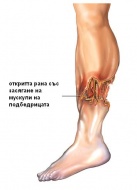

S86 Травма на мускулите и сухожилията на ниво подбедрица

Мускули и сухожилия на ниво подбедрица са класифицирани в три групи: - Задна мускулна група е състав...

S86.0 Травма на Ахилесовото сухожилие

Ахилесовото сухожилие е най-силното и най-дебелото сухожилие в човешкото тяло. Травма на Ахилесовото...